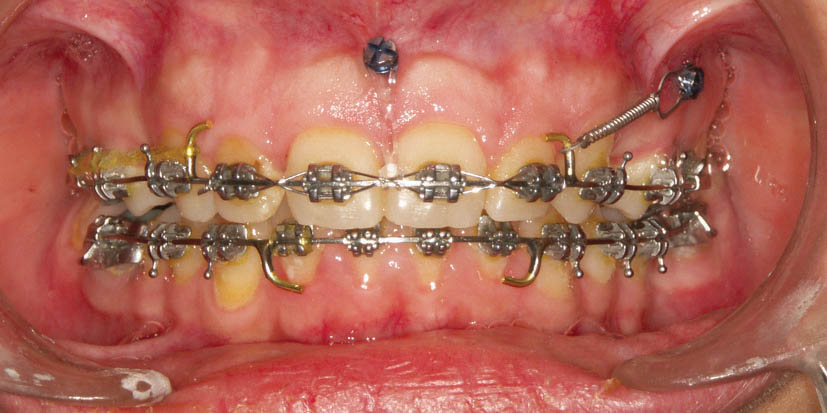

شکل 224-1: شکایت بیمار از پروتروژن. برای حرکت دیستالی سگمنت قدامی پرمولرها کشیده شدند.

شکل 225-1: برای اینکه مانع مزیالی شدن خلفیها بشویم تمام نیروها روی مینی اسکرو اعمال گردید و سگمنت قدامی تمام فضای به دست آمده از کشیدن پرمولرها را استفاده نمود.